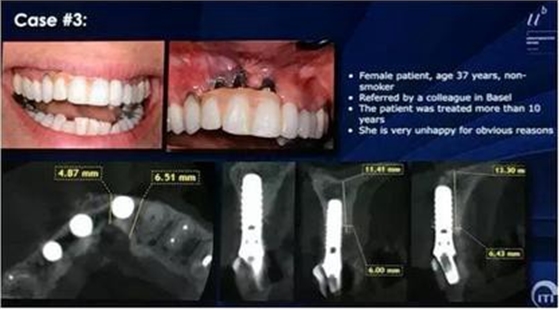

病例3:該病例三顆種植體植入位置偏頰,已經(jīng)發(fā)生了垂直向吸收。垂直向的骨增量技術(shù),是一個高風(fēng)險、高并發(fā)癥的治療,Danial Buser教授推薦最好進(jìn)行水平向的骨增量,垂直向缺損的恢復(fù)可以交給修復(fù)醫(yī)生通過修復(fù)手段彌補。

治療方案:使用BTI器械取出3顆種植體,缺損區(qū)行骨移植及全厚瓣軟組織移植,將14牙冠截到牙槽嵴水平使軟組織能愈合覆蓋根面;3~4個月后,在手術(shù)導(dǎo)板引導(dǎo)下行種植體植入同期GBR。第一次手術(shù)后,患者戴用可摘局部義齒。由于該患者的設(shè)計方案是種植體支持的帶有齦瓷的固定修復(fù)體,該義齒可以讓患者在某種程度上感受該治療方案的效果。種植體植入后,換成牙支持式壓膜臨時修復(fù)體。